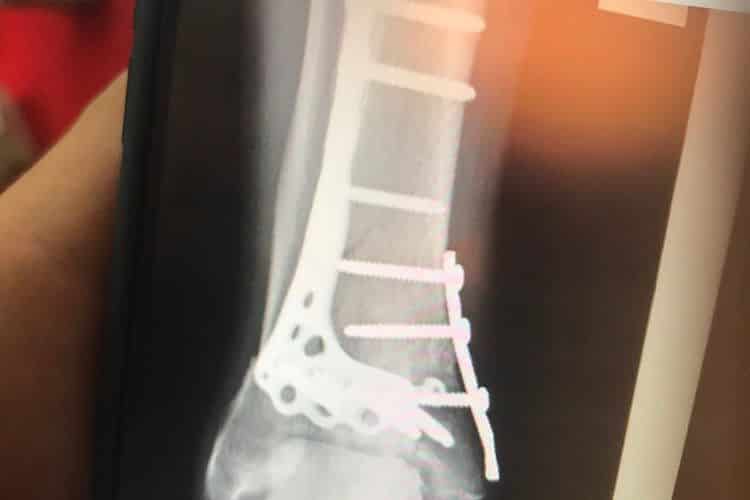

Un aveu fait sur le site Speedweek et formulé ainsi : « j’ai plus de problèmes avec la cheville et les nerfs du pied maintenant qu’en début de la saison » a déclaré Crutchlow. « J’ai déjà parlé aux médecins de l’enlèvement du métal. Mais ce ne sera probablement pas avant la fin de l’année ». La grande plaque de métal située à l’arrière de la cheville cogne presque à la surface de la peau. Au total, il porte presque un kilogramme de métal léger à cet endroit du corps.